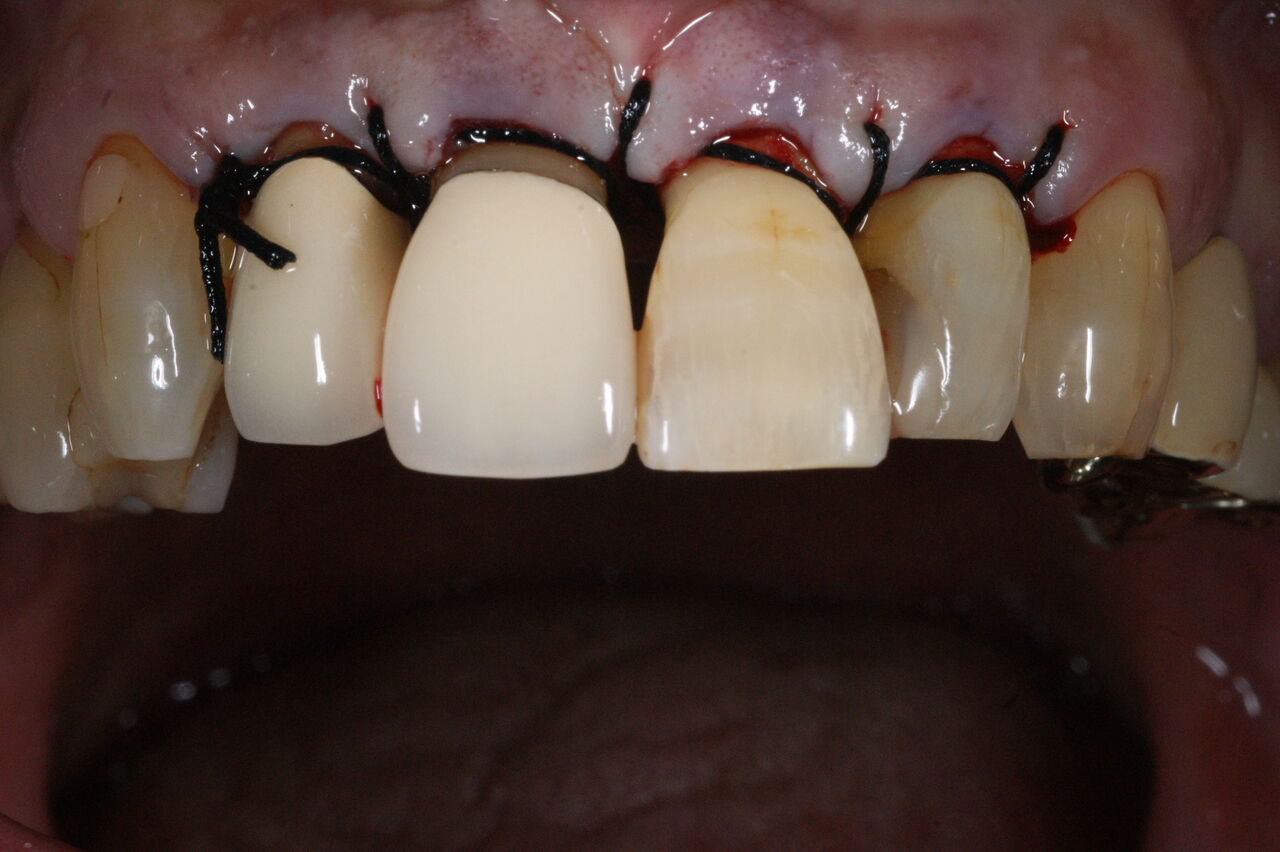

(歯周外科手術時口腔内写真。これ以上の資料は実際に掲載されたブログでご確認下さい!)

前回のブログの概略を説明しますと、患者さんは60歳、男性、会社員、上顎前歯部が普段はなんともないが、時々歯が浮き歯肉が腫れ噛みにくくなるものの、少しするとなおってしまう。

通法にしたがい、初期治療としてブラッシング、スケーリング、ルート プレーニングを行い、再評価したところ、歯周ポケットの深さが残った。浅くするには、原因となっている歯石を除去するための外科処置が必要であることを説明したところ、同意が得られ依頼されたので施行するに至った。

上図は手術時当該部位のデータと縫合時口腔内写真